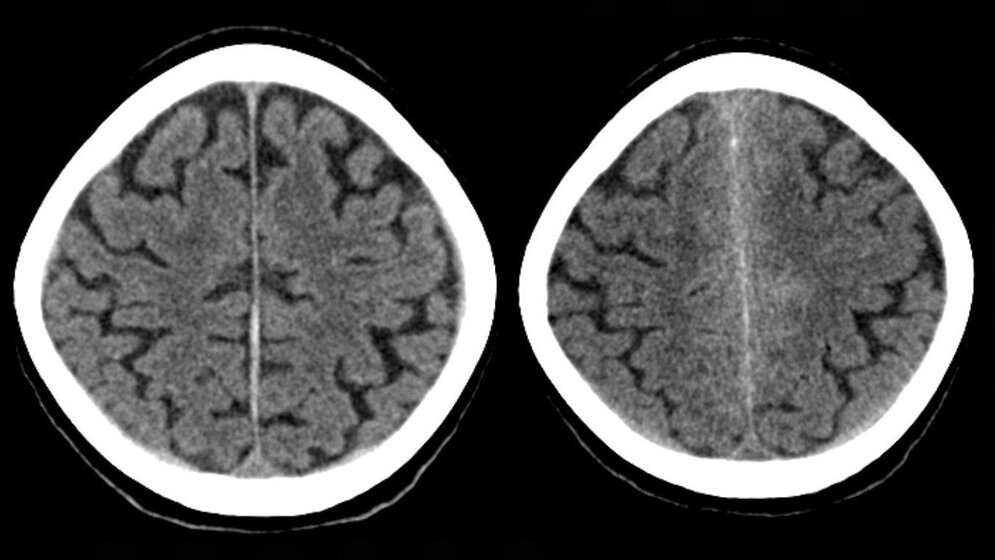

Bei Patientinnen und Patienten mit einer Subarachnoidalblutung – bei der sich die Blutung großflächig zwischen den umgebenden Häuten des Gehirns ausbreitet – kann es nach etwa einer Woche zu Komplikationen kommen. Jeder dritte bis vierte Patient zeigt dann Symptome eines ischämischen Schlaganfalls, also eines Schlaganfalls infolge einer Mangeldurchblutung. Dahinter stecken Mechanismen, die durch die molekularen Zerfallsprodukte der vorangegangenen Hirnblutung ausgelöst werden. Diese lösen elektrochemische Entladungswellen im Hirngewebe aus, auch „Spreading Depolarization“ genannt. Die betroffenen Hirnareale benötigen dann sehr viel Energie, um wieder in den Normalzustand zurückzukehren.

Im gesunden Gehirn sind normale Entladungen von Nervenzellen mit der Blutversorgung gekoppelt: In aktiven Bereichen werden die Gefäße geweitet. Nach einer Subarachnoidalblutung können die Signalkaskaden zwischen Nervenzellen und Blutgefäßen jedoch gestört sein. Eine Nervenzellentladung löst dann eine extreme Verengung der Gefäße aus. In der Folge fehlt den Nervenzellen die Energie, um sich wieder aufzuladen. Verbleiben die Nervenzellen zu lange in einem entladenen Zustand, beginnen sie irgendwann abzusterben. Bei der Messung der elektrischen Hirnaktivität zeigt sich dann eine riesige, sehr langsame Spannungsänderung, ein sogenanntes negatives ultralangsames Potential. Man spricht in diesem Fall von „terminaler Spreading Depolarization“.

„Vor zwei Monaten konnten wir die terminale Spreading Depolarization erstmals beim Menschen nachweisen, bei Patienten mit Herzkreislaufstillstand. Jetzt konnten wir zeigen, dass sie auch bei Patienten mit Hirninfarkten nach Subarachnoidalblutung auftritt“, erläutert Prof. Dr. Jens Dreier vom Centrum für Schlaganfallforschung Berlin der Charité. Prof. Dreier und sein Team werteten die Daten von elf Patienten aus und verglichen die Ergebnisse mit Erkenntnissen aus tierexperimentellen Untersuchungen. Die Depolarisierungswellen zeigen einen gestörten Energiehaushalt an. Das negative ultralangsame Potential ist die elektrophysiologische Entsprechung des Infarkts, also des Gewebsuntergangs als Folge einer Mangeldurchblutung.